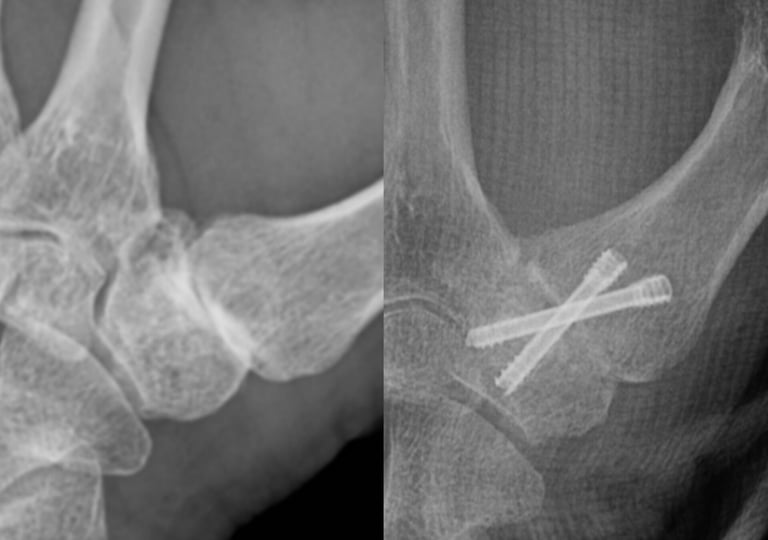

Estabilidad definitiva para casos avanzados

La artrodesis trapeciometacarpiana por artroscopia permite tratar la rizartrosis avanzada mediante la fusión controlada de la articulación, preservando la biomecánica del pulgar y reduciendo el dolor de forma definitiva. La asistencia artroscópica facilita una preparación precisa de las superficies articulares y una mínima agresión tisular, mientras que los tornillos canulados cruzados aportan una fijación sólida y fiable.

Rizartrosis avanzada o colapso severo con deformidad establecida (Eaton III–IV).

Pacientes jóvenes o muy activos, menos de 50 años, que priorizan fuerza y estabilidad sobre la movilidad.

Pacientes con trabajo manual intenso donde se requiere una solución definitiva y resistente.

Articulación con inestabilidad marcada o fracasos previos de otras técnicas.

Buena calidad ósea para garantizar la consolidación.